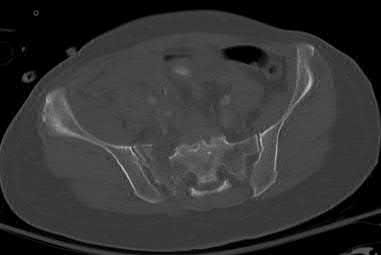

A 45-year-old man is involved in a high-speed motor vehicle collision. The AP pelvis radiograph demonstrates an acetabular fracture. According to the Letournel classification, which of the following radiographic lines is typically disrupted in an isolated transverse acetabular fracture?

Correct Answer: Both the iliopectineal and ilioischial lines

Explanation:

A transverse acetabular fracture is an elementary fracture pattern that involves a single fracture line crossing the acetabulum horizontally. Because it bisects both the anterior and posterior columns of the acetabulum, it disrupts both the iliopectineal line (anterior column marker) and the ilioischial line (posterior column marker) on a standard AP pelvis radiograph.